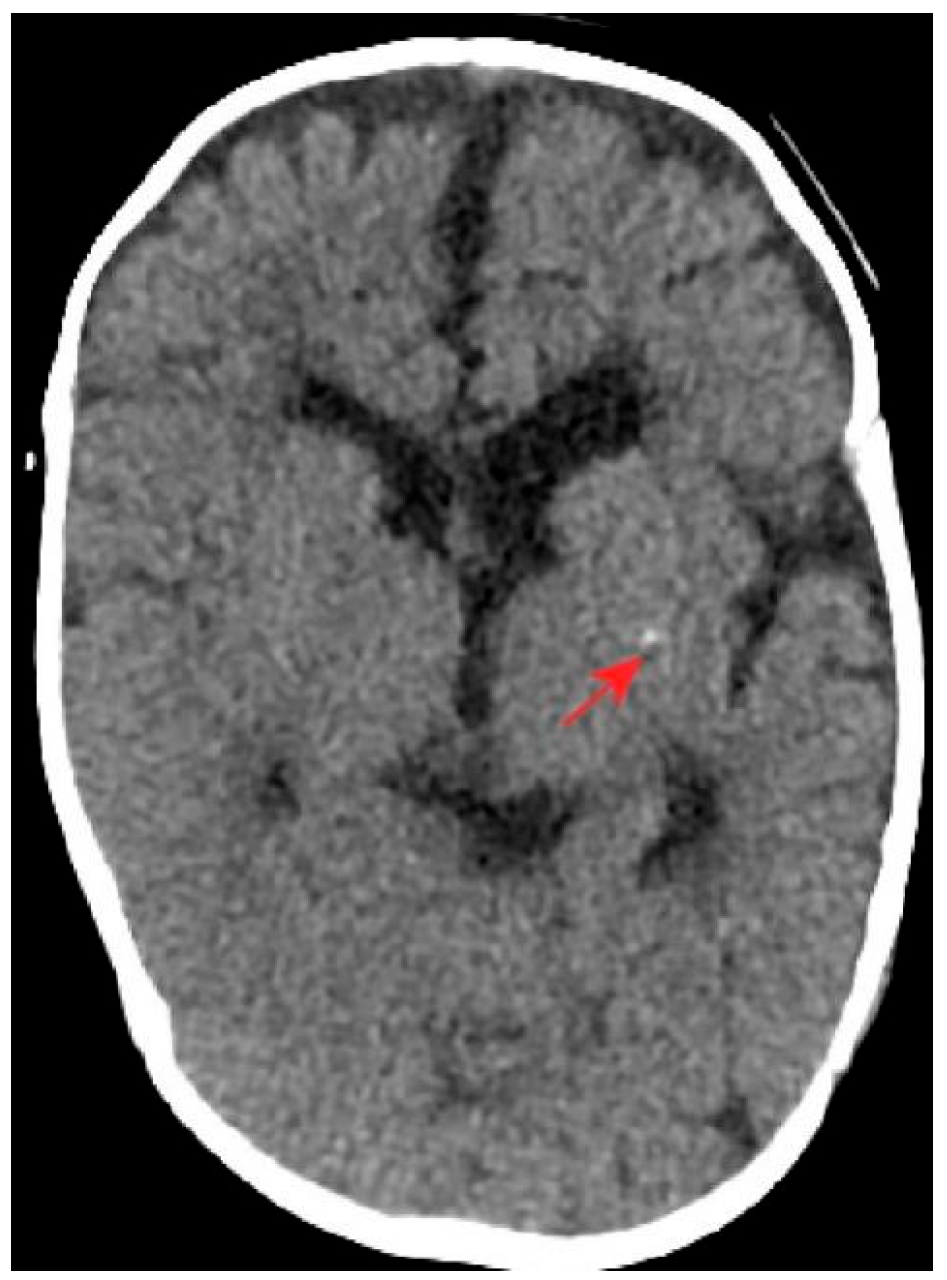

3.3. Imaging

| Neurological | Birth | Seizures, muscle tone abnormalities, basal ganglia calcification, brain dysplasia | Adrenocorticotropic hormone/prednisone acetate/topiramate/sodium valproate/levetiracetam; seizures were well-controlled |